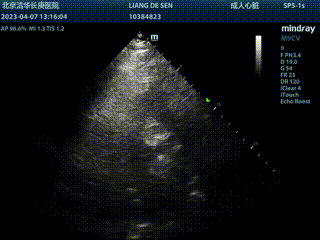

就诊于本院急诊:查心肌损伤标物升高,心电图示完全性右束支阻滞,胸前导联V3-V6 ST段压低,行超声心动图检查示左心增大,室间隔及左室壁增厚,主动脉瓣钙化,重度狭窄,轻度关闭不全,二尖瓣后叶瓣环钙化并少量反流,左室整体收缩及舒张功能减低,考虑诊断为“主动脉瓣重度狭窄”。

平均压差79mmHg,峰值流速6.69m/s,EF值66%,主动脉瓣钙化重度狭窄伴轻度关闭不全,二尖瓣后叶瓣环钙化并少量反流,左心增大,室间隔及左室壁增厚。